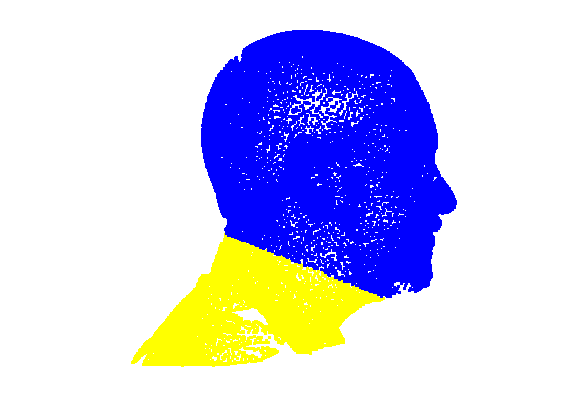

5.3 Face and cranium segmentation

Fitting a sparse model to the head scan data normalises its pose to frontal. Since we use landmarks that localise the majority of the facial area (rather than just inner eyes and nose), we can reliably position a scale-adaptive mesh cropping plane. We choose a distance below the chin landmark, that is some proportion of the face length, defined by the distance from the nasion landmark to the chin landmark. This gives a cropping plane that scale-adapts to the size of the head and it is aligned such that it is at some fixed angle (eg. 40 degrees, chosen experimentally) in the Y-Z plane. This is then used to remove the neck and shoulder area of the scan, as shown in Fig. 10.